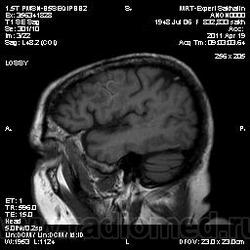

склоняюсь к кровизлиянию в левой теменной долей, начало перехода острой стадии в раннюю подострую( по периферии определяется повышение МРС по Т1 ВИ -метгемоглобин). Справа -старые кортикальные постишемческие глиозно-атрофические изменения. Контрастируется , вероятно за счет формирования участков ангионеогенза.

Это демиелинизирующий процесс, острая стадия, причем с геморрагическим пропитыванием в центре пораженных участков. В принципе, соответствует тяжелому рассеяному склерозу, хотя может быть и геморрагическая форма ОДЭМ. Также могут быть мозговые проявления системного васкулита: надо знать анамнез.

На фоне ДЭП изменений МР-картина ОНМК по ишемическому типу в бассейне ЛСМА с участками геморрагического пропитывания. Аналогичный участок но в более поздней фазе в задних конвнкситальных отделах правой теменной доли.

О.С., я согласен, что контрастирование нехарактерно для ОНМК, ведь в подострую стадию инфаркта наблюдается, как правило, гиральный тип усиления. Плюс, на ОНМК непохоже то, что поражено почти только белое вещество, а кора интактна. И потом, при такой локализации инфаркта обязательно должна быть яркая клиника, и уж никак не только "головная боль".

Что касается снимочков мне кажется что зона патологического сигнала в левой гемисфере можно расценить как подострую стадию ОНМК с геморрагическим пропитыванием, справа как последствия ОНМК. При чем множественные очаги скорей всего как проявление ХМНК. И обязательно рекомендовать контрольное МРТ в динамике . Если это действительно ОНМК на фоне лечения отек уйдет и будет формированиться зона кистозно-глиозных изменений, а если отек будет нарастать значит надо думать о объемном процессе.

ОНМК по геморрагическому типу, почти классика.